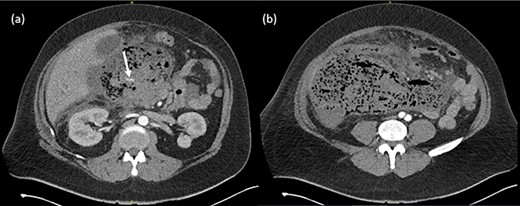

He was hemodynamically stable and afebrile on presentation, however deteriorated rapidly with tachycardia (HR140), hypotension (<100 mmHg systolic) and temperature of 39.0°C. Examination revealed a grossly distended, rigid abdomen. Inflammatory markers were elevated with a white cell count of 35.3 × 109/L and C-reactive protein of 326 mg/L. Serum lipase was 384 U/L. Imaging demonstrated a large peripancreatic collection with extensive gas loculations and active arterial blush and he was taken for emergent surgery (Fig. 1).

(a) Arterial phase CT axial view demonstrating peripancreatic collection with extensive gas loculations and active arterial blush (white arrow). (b) Extensive peripancreatic collection at the level of the aortic bifurcation.